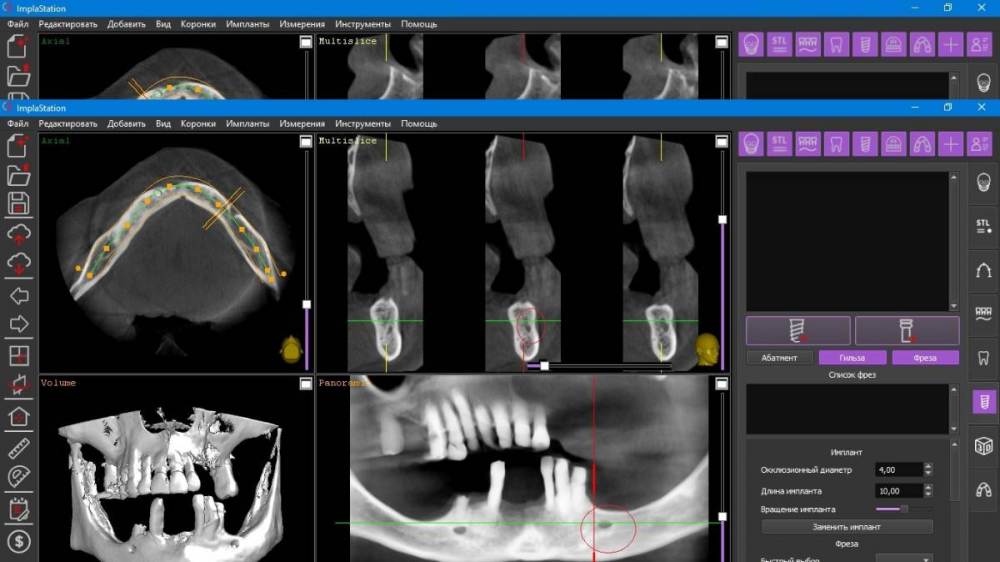

Fatal Опубликовано 6 сентября, 2021 Поделиться Опубликовано 6 сентября, 2021 (изменено) Доброго времени суток коллеги. Есть один клинический случай, где я планирую сделать все на 4, возможно с немедленной нагрузкой. Столкнулся с тем, что foramen mentale четко видно, но ''веточка'' от него выходит еще более медиально особенно в 4 квадранте (фото прилагаю) и тогда не получается поставить имплант в области 44 зуба под углом, что б шахта выходила более дистально для меньшего рычага. (планировалось закончить пятыми зубами или 6ки размоделировать как премоляры). Атрофия значительная в жевательном отделе, костные пластики не планируются. Импланты на фото расставлены примерно, для понимания картины. Вопрос: как ставить имплант в области 44 зуба, если '' веточка'' ментале выходит еще более медиально, также с зоной безопасности в 2 мм? (тогда я упрусь в имплант в области 41-42) -- 4 фото, обведено красным Изменено 6 сентября, 2021 пользователем Fatal Ссылка на комментарий

Александр07 Опубликовано 10 сентября, 2021 Поделиться Опубликовано 10 сентября, 2021 Ветку честно говоря не увидел, я бы больше наклонил имплантат, и длиннее, платформу импл максимально над менталисом расположить нужно постараться , это наиболее дистальное возможное положение Ссылка на комментарий